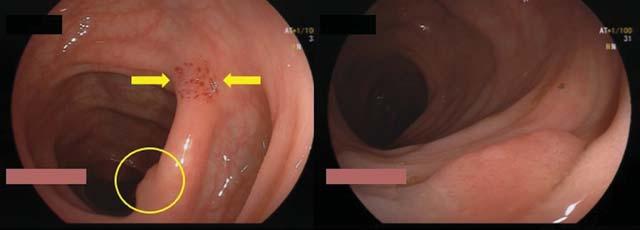

Suction Mark Technique for Identifying And Resecting Flat Colon Polyps